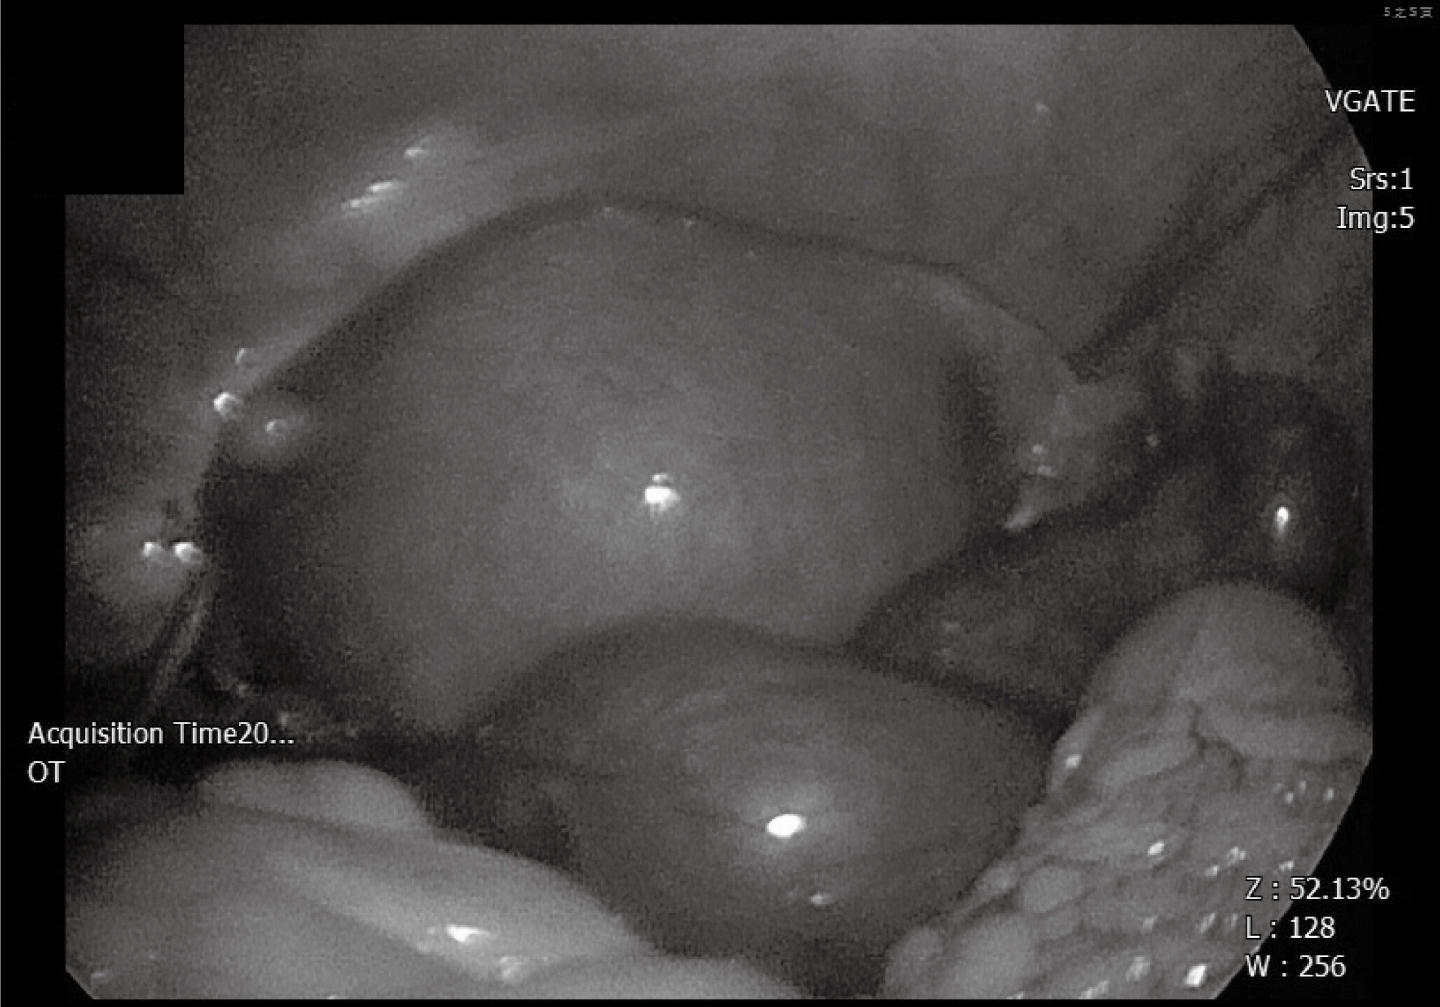

這位患者再度接受腹腔鏡手術,不過這次手術對象是巧克力囊腫 這時的輸卵管已經比較正常,也在這個手術之後,她願意進入試管嬰兒療程。(正常的輸卵管樣子)

一路看著這位患者曲折離奇的懷孕過程,我們處理了子宮外孕及巧克力囊腫的兩次腹腔鏡手術,治療好子宮外孕的輸卵管。子宮外孕手術的時候,選擇保留只剩一邊的唯一輸卵管。巧克力囊腫手術的時候,合併處理骨盆腔沾黏,才得以救回這麼肥的輸卵管,因此就算只剩下單邊,仍有可能發生自然懷孕